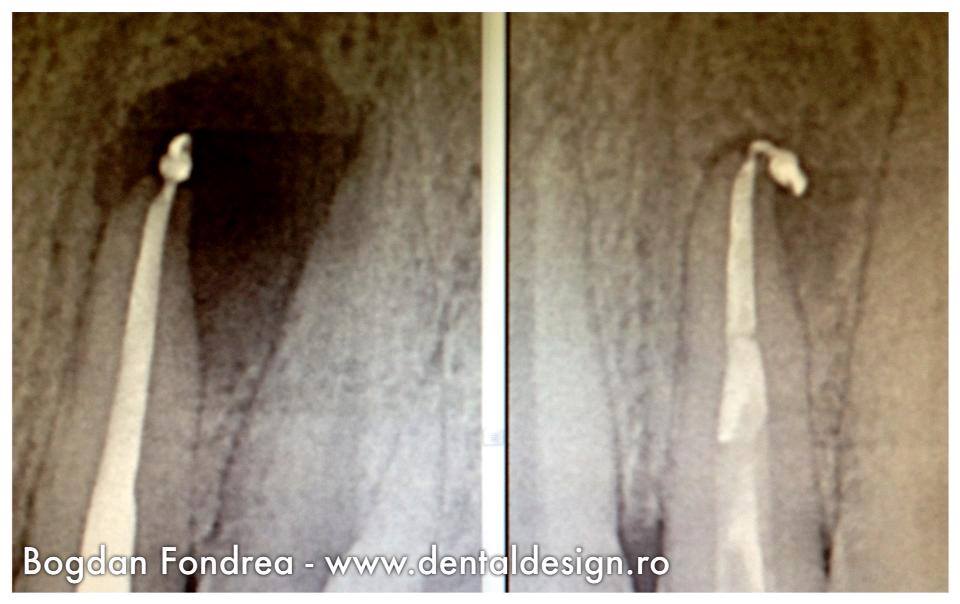

Cazul 3 – se verifică tratamentul efectuat și după câteva luni se dă verdictul: dintele a fost salvat. Am reușit.